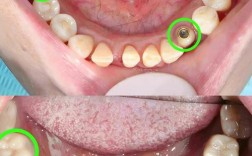

(图片来源网络,侵删)- 基台松动: 连接种植体和牙冠的基台如果本身没有拧紧到位,或者基台与种植体连接的螺纹损坏,会导致牙冠无法稳固。

- 检查种植体基台:确认基台是否在位、是否松动、是否损坏、连接螺纹是否完好。